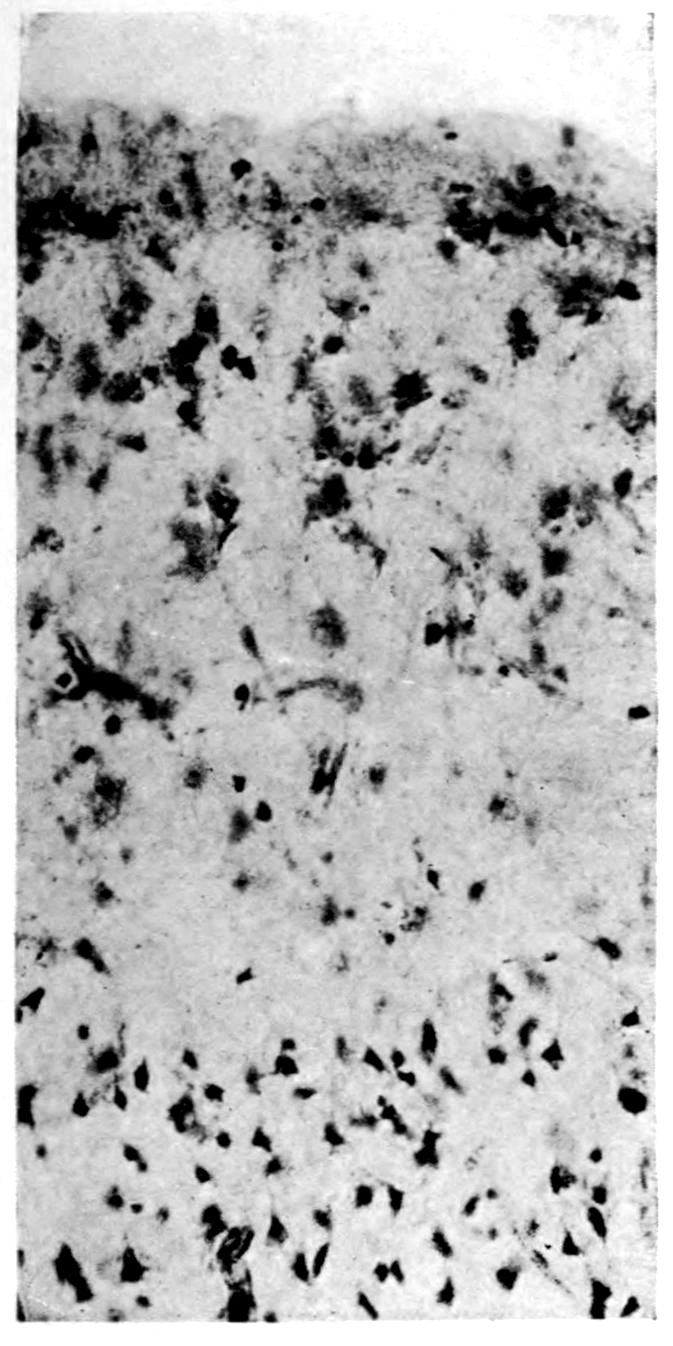

A. Normal postcentral cortex. (Compare B.)

B. Nerve cell losses. Perivascular deposits of mononuclear cells, amongst which are numerous plasma cells. Note decrease in number of nerve cells. Note irregular disposition of nerve cells. From paretic neurosyphilis.

Microscopic findings are here presented merely in sufficient detail to establish the diagnosis. The left superior frontal gyrus shows extensive and somewhat irregular cellular and fibrillar gliosis of the plexiform layer, together with an increase of thickened vessels having lymphocytes and plasma cells in their sheaths.

The perivascular infiltrations are most extensive in the lower layers of the cortex. The lamination is in places thoroughly obscured, except that representatives of the layer of large external pyramids are almost always demonstrable.

The layer of medium-sized pyramids has undergone more numerical loss of elements than have the other layers.

41Characteristic and constant in paretic neurosyphilis is the Plasmocytosis and Lymphocytosis, Perivascular in distribution about small cortical vessels. There is also a characteristic (though characteristically less prominent) Plasmocytosis and Lymphocytosis, Meningeal in distribution. The pleocytosis of the spinal fluid, almost constant though variable in amount in life, is an indicator of the meningeal picture and less directly of the parenchymatous picture.